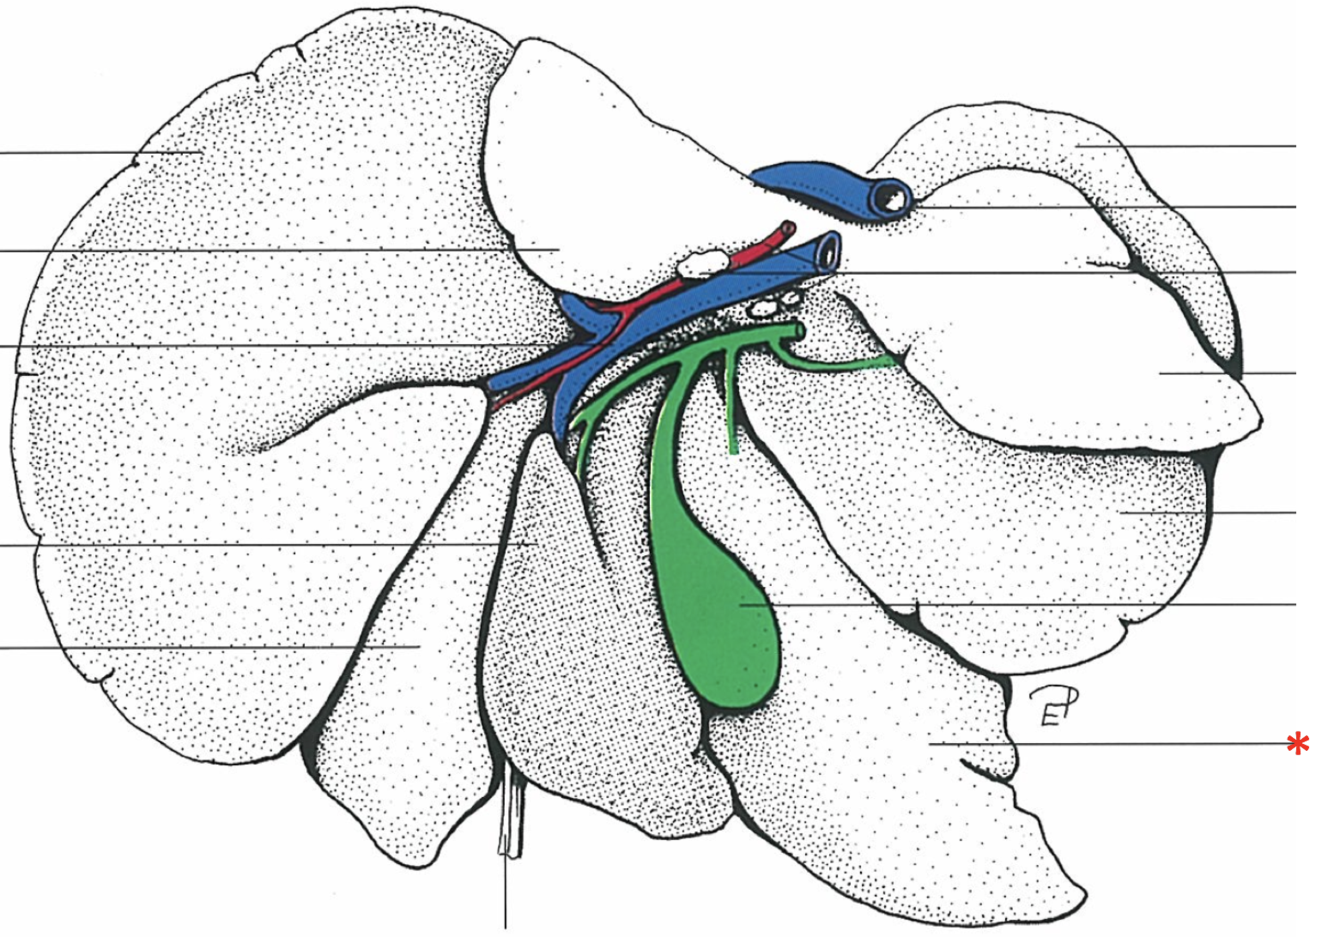

Porta hepatis

- With v. portae et a. hepatica

Lobus caudatus

Lobus quadratus

Lobus hepatis sinister medialis

Lobus hepatis dexter medialis

Lobus hepatis dexter lateralis

Proc. caudatus

V. portae

Proc. papillaris

Lobus hepatis sinister lateralis

Impressio renalis

What is shown? Give the Aspect.

Liver of a Cat

Facies diaphragmatica